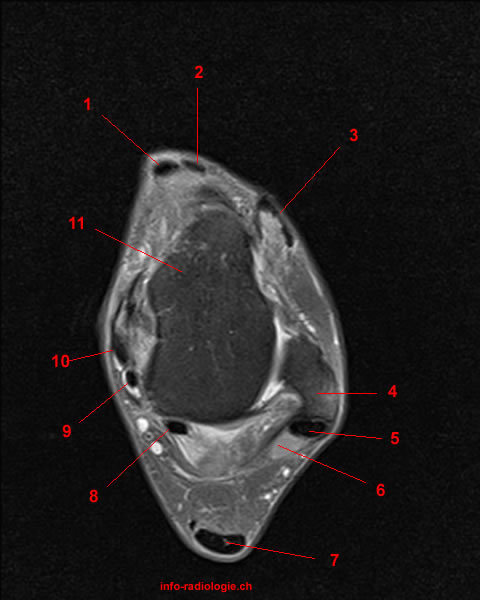

What are the main ligaments of the ankle?

Identify the tendons.

Anterior group, from medial to lateral: 1. Tibialis anterior, 2. Extensor hallicus longus, 3. Extensor digitorum longus.

Lateral group: 5. Peroneus longus, 6. Peroneus brevis.

Medial group, from anterior to posterior: 10. Tibialis posterior, 9. Flexor digitorum longus, 8. Flexor hallucis longus.